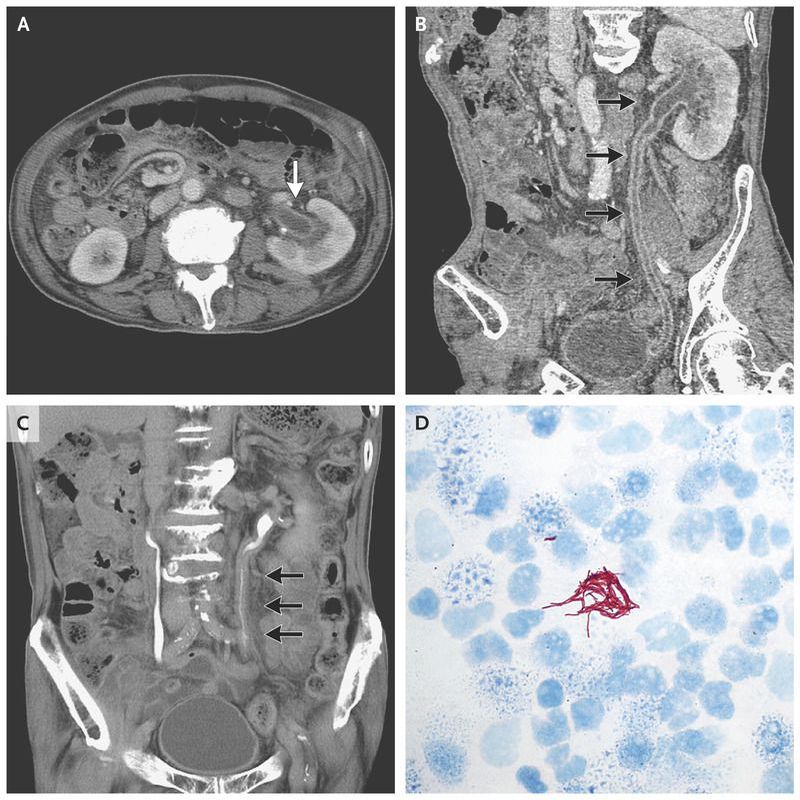

A 76-year-old man with diabetes and a 2-year history of mediastinal lymphadenopathy of unknown cause presented with fever and fatigue. Pyuria was seen on urinalysis. Contrast-enhanced computed tomography (CT) of the abdomen showed mild dilatation of the left renal pelvis and thickening of the ipsilateral ureteral wall (Panels A and B, arrows); the excretory phase on CT showed mild narrowing of the left ureter (Panel C, arrows). He was treated with a beta-lactam antibiotic, but pyuria and fever persisted. The results of a urine culture were negative. Urinary acid-fast staining revealed the presence of acid-fast bacilli (Panel D). A polymerase-chain-reaction assay for Mycobacterium tuberculosis was positive. Patients with urinary tract tuberculosis can present with dysuria and hematuria, though many patients are asymptomatic, with only sterile pyuria, with or without microscopic hematuria. Urogenital tuberculosis may cause complications, such as ureteral strictures, oligospermia in men, and vaginal bleeding in women. The patient was treated with multiple-drug therapy for tuberculosis, and his symptoms abated.